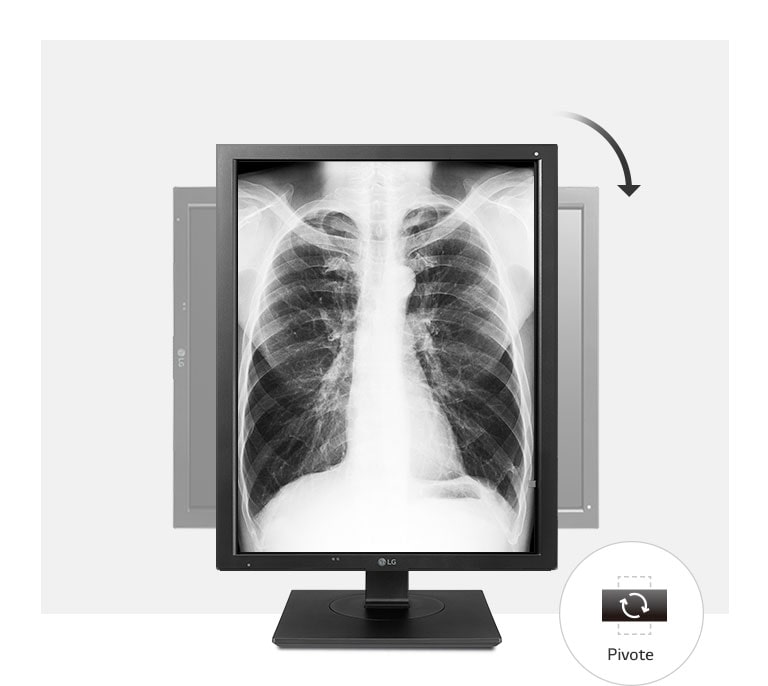

Calidad de imagen precisa

diagnóstico preciso de las imágenes médicas de la TC y la Angiografía, ya que le permite

a los médicos distinguir incluso los pequeños detalles con facilidad.